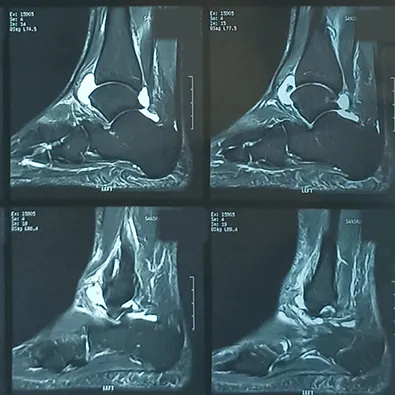

Returning home, the ankle MRI scans revealed a broken cartilage which required surgery and a lengthy period of recovery which included two phases:

A full recovery back to proper functionality can vary between three to six months.

MRI Film of Injured Ankle